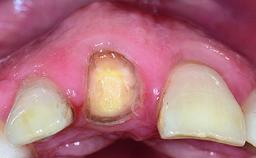

A 32-year-old female Caucasian patient with a compromised maxillary right central incisor was referred to us by a general dentist. Her chief complaints were discomfort and mobility of tooth 11 with unsatisfactory esthetics due to discoloration. The patient reported a previous trauma, some years earlier, as the origin of pathology on the afflicted tooth. Anamnesis was negative for any other dental or periodontal pathology in the remaining dentition. The patient did not take any medication and reported to be a light smoker (5–10 cigs/day). She had high esthetic expectations of her treatment. The extraoral examination revealed a high smile line with full exposure of her maxillary teeth and surrounding soft tissue in the area between the second premolars.

Bone Augmentation Horizontal|Simultaneous|Staged

Augmentation Materials Autogenous chips|Xenogenous|Membrane

Soft Tissue Grafting Staged